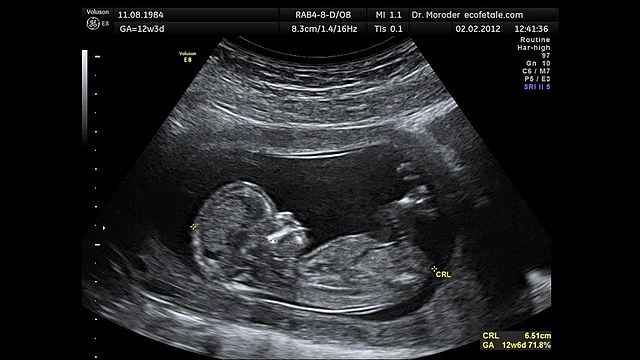

• Semana 12

Semana 12

La piel es delgada casi transparente sus órganos comienzan a funcionar, y apenas mide 8 centímetros, pero esta completamente formado